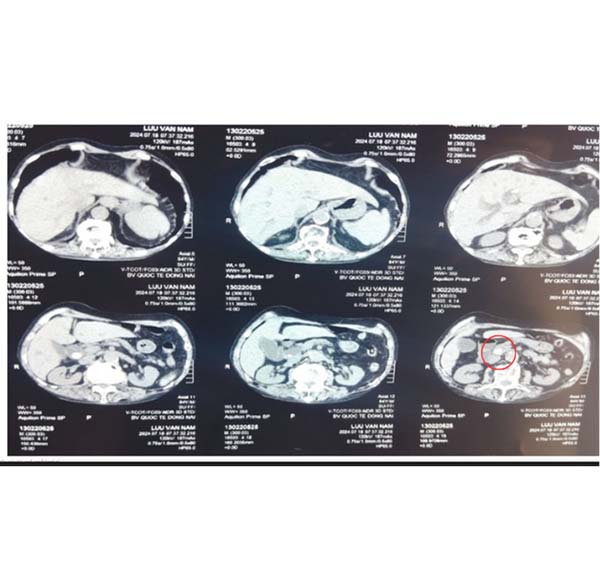

Sau đó, bệnh nhân được chụp CT scan bụng, phát hiện sỏi khoảng 15mm ở đoạn cuối ống mật chủ, sỏi ở ống gan chung và nhánh trái của gan khoảng 12mm. đường mật trong và ngoài gan giãn, ít sỏi bùn túi mật. Xét nghiệm máu có Bilirubin toàn phần và trực tiếp tăng chiếm ưu thế.

Sỏi ống mật chủ. Ảnh: Bệnh viện cung cấp